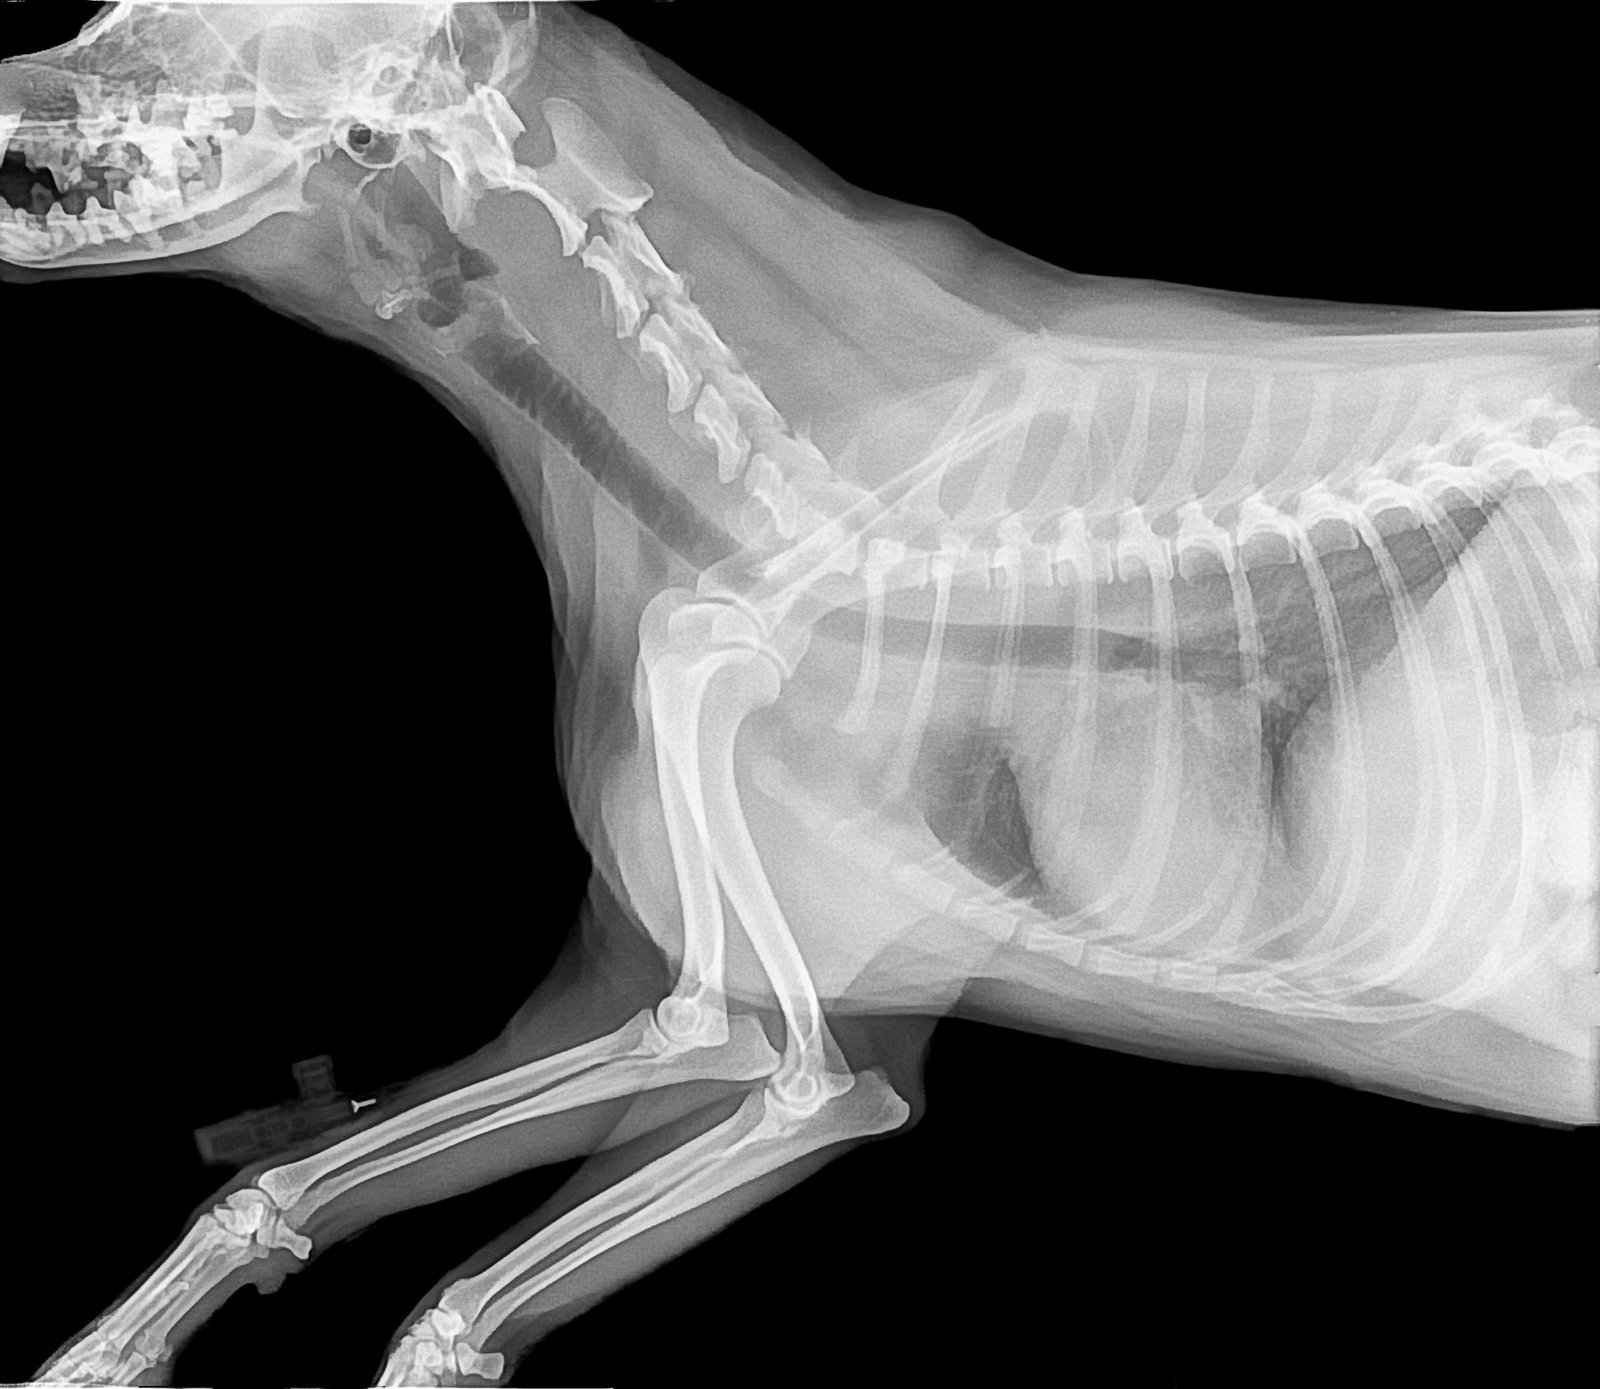

VETERINARY

All our services can be adapted to clinical veterinary medicine.

radiography 2010129